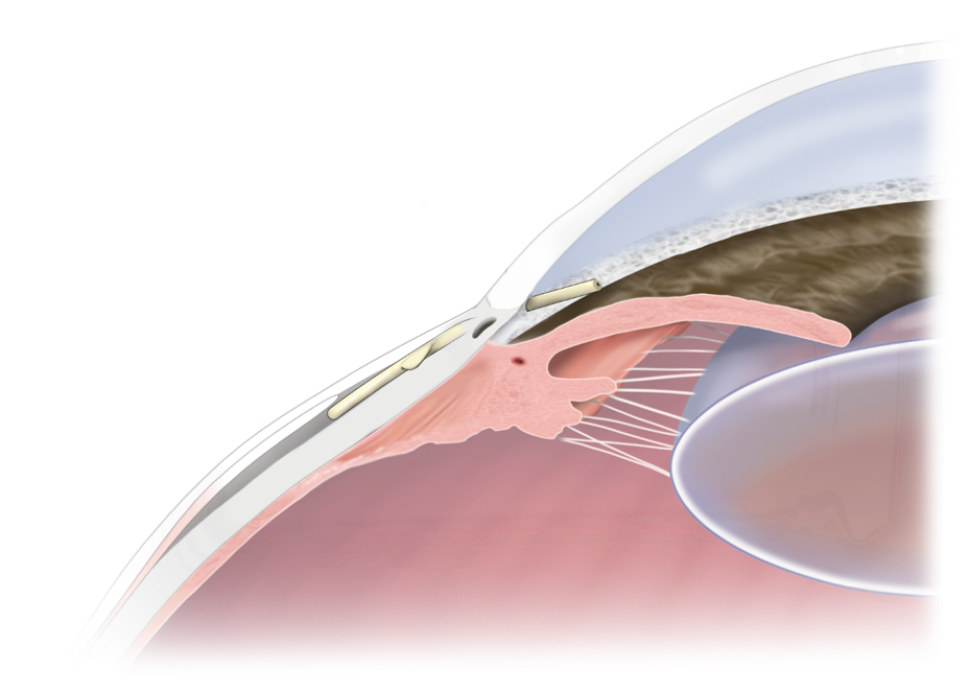

Το Xen Gel Stent® είναι ένας υδρόφιλος μικροσωλήνας μήκους 6mm με εσωτερική διάμετρο 45μm ή 63μm . Είναι φτιαγμένο από ζελατίνη και και προσαρμόζεται στον ιστό χωρίς να προκαλεί αντίδραση ίνωσης γύρω από αυτό.

Εγκρίθηκε από τον FDA το 2016 για χρήση σε πρωτοπαθή γλαυκώματα ανοιχτής γωνίας, ψευδοαποφολιδωτικά και μελαγχρωστικά γλαυκώματα που είναι ανθεκτικά σε φαρμακευτική θεραπεία ή επί αποτυχίας προηγούμενης αντιγλαυκωματικής χειρουργικής επέμβασης. Ανήκει στην κατηγορία των MIBS - Microinvasive Bleb Surgery, των επεμβάσεων δηλαδή όπου γίνεται πλήρης παράκαμψη της γωνίας αποχέτευσης και απευθείας αποχέτευση του υδατοειδούς υγρού κάτω από των επιπεφυκότα με την αντίστοιχη δημιουργία φυαλλίδας διήθησης (bleb surgery).

Preserflo™

Το εμφύτευμα Preserflo™ είναι κατασκευασμένο από ένα βιοσυμβατό υλικό που ονομάζεται SIBS (poly(styrene-block- isobutylene-block-styrene)). Λόγω του ειδικού σχεδιασμού του, με διαστάσεις 8.5mm μήκος και 70μm εσωτερική διάμετρος, η πιθανότητες της υποτονίας μειώνονται. Έχει παρόμοιο μηχανισμό δράσης με το εμφύτευμα Xen με τη δημιουργία διηθητικής φυσαλίδας και επιτυγχάνει μειώσεις στην ενδοφθάλμια πίεση εφάμιλλες με αυτές της τραμπεκουλεκτομής.

Πως γίνεται η συγκεκριμένη επέμβαση;

Η επέμβαση γίνεται σε μονάδα ημερήσιας νοσηλείας με τον ασθενή να γυρίζει σπίτι του την ίδια ημέρα. Πραγματοποιείται συνήθως με περιοχική αναισθησία και μέθη υπό την επίβλεψη αναισθησιολόγου. Γίνεται διατομή και προσεκτικοί χειρισμοί του επιπεφυκότα και της κάψας του Tenons, χρήση αντιμεταβολιτών τύπου Μιτουκίνης C και προσεκτική τοποθέτηση του εμφυτεύματος στο πρόσθιο θάλαμο δια μέσου του σκληρού χιτώνα και της γωνίας αποχέτευσης. Το εγγύς τμήμα αυτού μένει κάτω από την κάψα του Tenons.